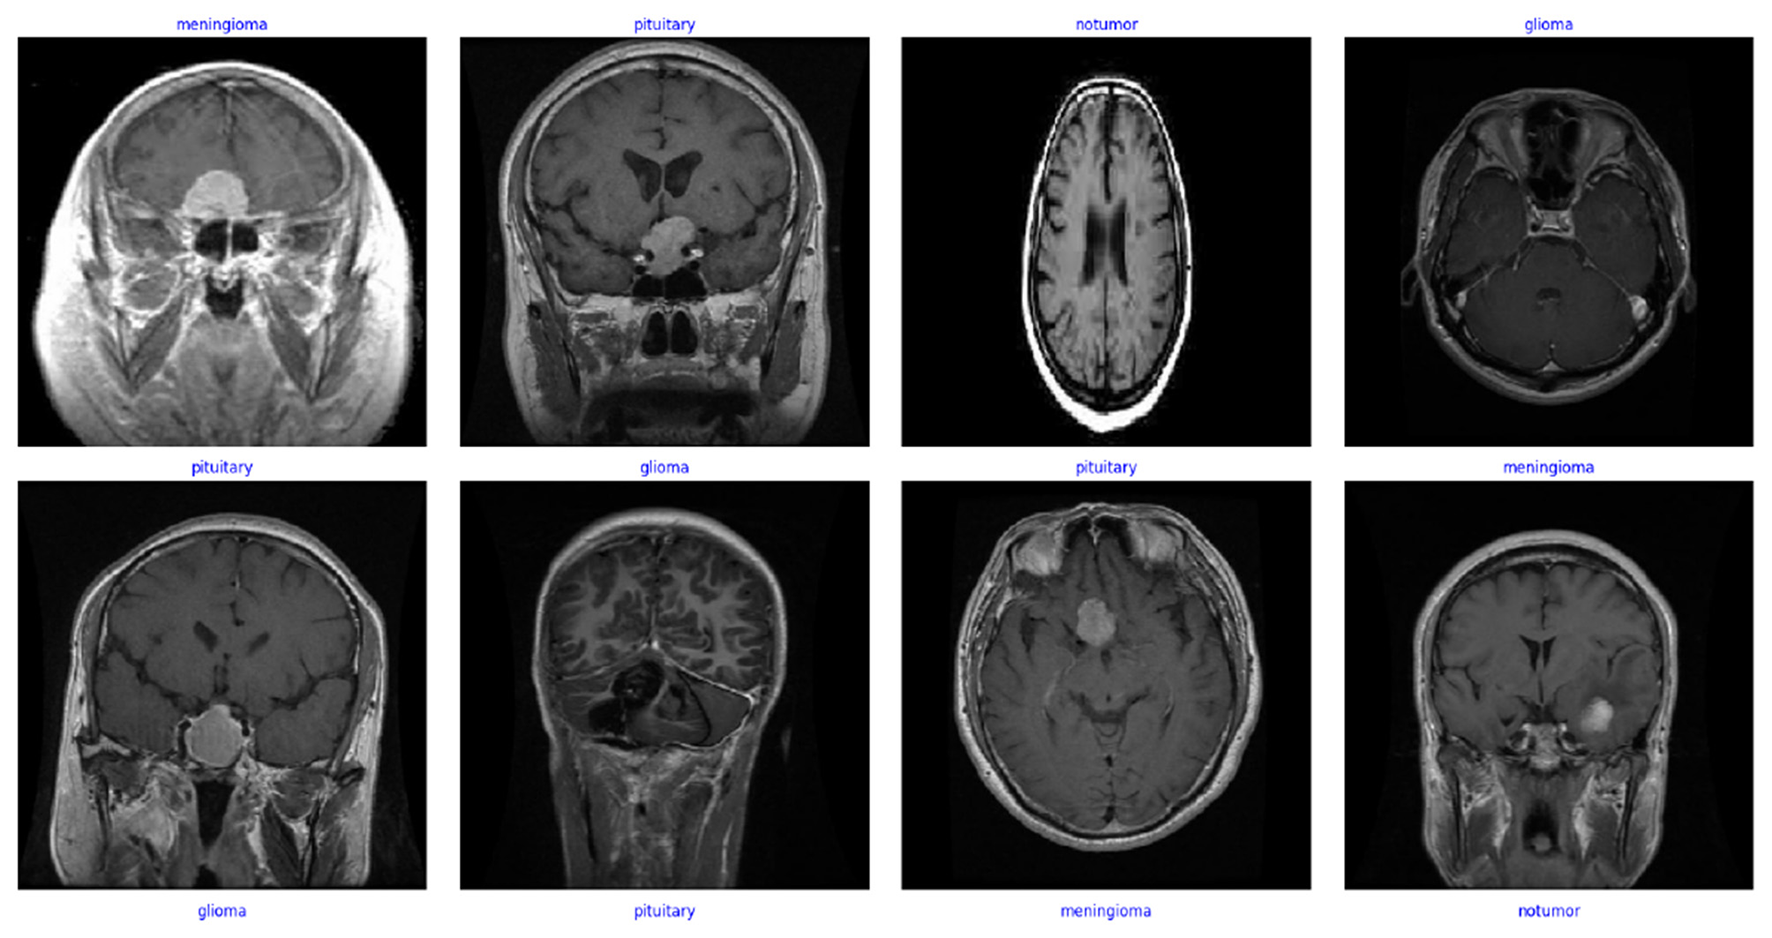

Brain tumors are a life-threatening condition, and their early detection is crucial for effective treatment and improved survival rates. Traditional manual evaluation techniques, such as expert radiologist assessments and visual inspections, are widely used for diagnosing brain tumors. While these methods can be highly reliable, they are often time-consuming, prone to human error, and challenging to scale for large datasets. Consequently, there is a growing demand for computer-aided diagnostic systems to overcome these limitations and deliver fast, accurate, and scalable solutions. Despite these promising advancements, the study highlights potential limitations, such as susceptibility to overfitting due to limited labeled data and the need for extensive hyperparameter tuning to generalize across diverse datasets. This paper proposes a scalable multi-class brain tumor classification framework optimized for small-form-factor devices. We introduced a novel lightweight custom convolutional neural network (CNN) that maintains high classification accuracy while significantly reducing computational complexity. We evaluated the capacity of the model by training and testing on five different datasets and the model performed well on all five. We saw great performance with the model on larger datasets, but it struggled when it came to smaller and imbalanced datasets. We achieved significant scores on the datasets, and we had the highest testing accuracy on Dataset-5 (99.67% training accuracy, 98.17% validation accuracy and 98.30% testing accuracy). What is important to note is that we had the lowest testing accuracy on Dataset-3 (99.99% training accuracy, 74.11% validation accuracy and 75.63% testing accuracy).. The proposed framework leverages state-of-the-art pre-trained deep learning models, including EfficientNetb3, ResNet-101, ResNet-50, Xception, AlexNet, DenseNet121, Swin Transformer, and our custom lightweight CNN model. Experimental evaluations demonstrate that EfficientNetb3 achieves the highest accuracy of 99.11%, while the custom lightweight CNN attains 98% accuracy with 4.1x fewer parameters and reduced training time. These results highlight the effectiveness of computer-aided approaches in achieving near-expert performance, making them suitable for integration into clinical workflows. This research paves the way for deploying efficient and scalable deep learning models in real-world medical applications to expand accessibility to accurate brain tumor diagnosis.